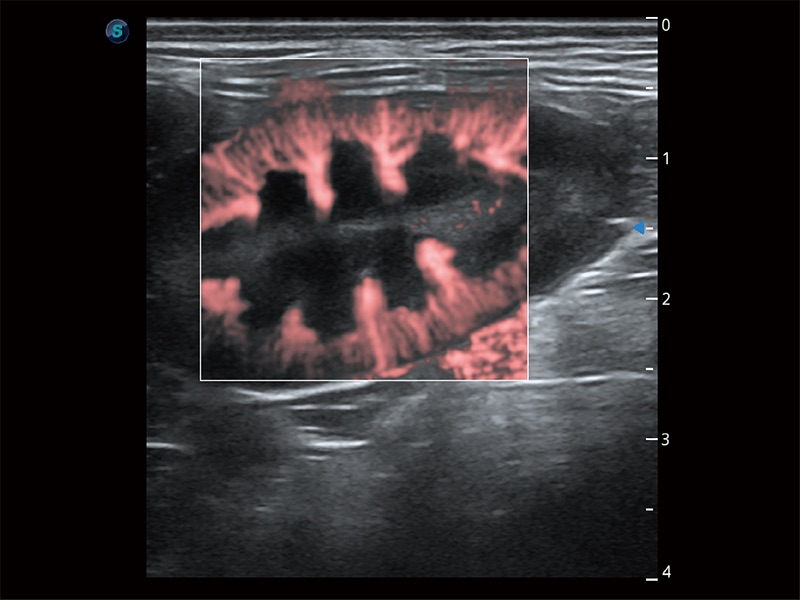

了若指掌 腹部/浅表解决方案

高性能和先进的临床应用工具可以为动物医生提供临床信心。ProPet 80 搭载了先进的腹部和浅表应用工具,帮助医生在日常临床实践中发挥前所未有的作用。

• Micro F 显微血流成像

极大提升超低速微细血流的检出能力,同时更精准地滤除软组织和超声信号,为兽用医生提供以往无法通过常规血流获得的疾病诊断信息。

• Bright Flow 立体血流成像

在传统二维血流成像的基础上,呈现血流的立体感,具有动感的生命力之美。即便是微小的血管也能轻松应对,提高了血流的视觉敏感性。

优异的基础图像

ProPet 80 全新的动物超声智能软件和丰富的探头群,为动物医生提供了高清晰度和精细分辨率的图像,无论在宠物、马科、畜牧还是实验室动物等应用中都可以轻松应对,为您的日常工作带来满意的体验。

(犬)肾脏显微血流